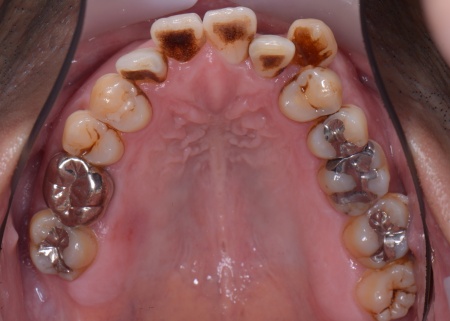

| カウンセリング | 拝見したところ、上下の歯は、ずれたりねじれたりしてデコボコに生えており、著しく歯並びが乱れていました。

またレントゲン撮影をして確認すると、右上前歯は顎の骨の中に埋まっている骨性埋伏(こっせいまいふく)の状態でした。 さらに、左下奥歯は重度の歯周病であり、歯を支えている骨が一部溶けていることが判明しました。 以上のことから、歯並びを整える矯正治療と歯周病の治療を併せて行う必要があると診断しました。 |